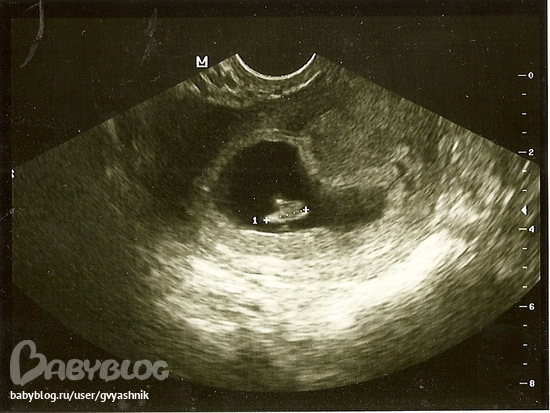

7-8 недель, самый первые осмотр. Длина 1 см))